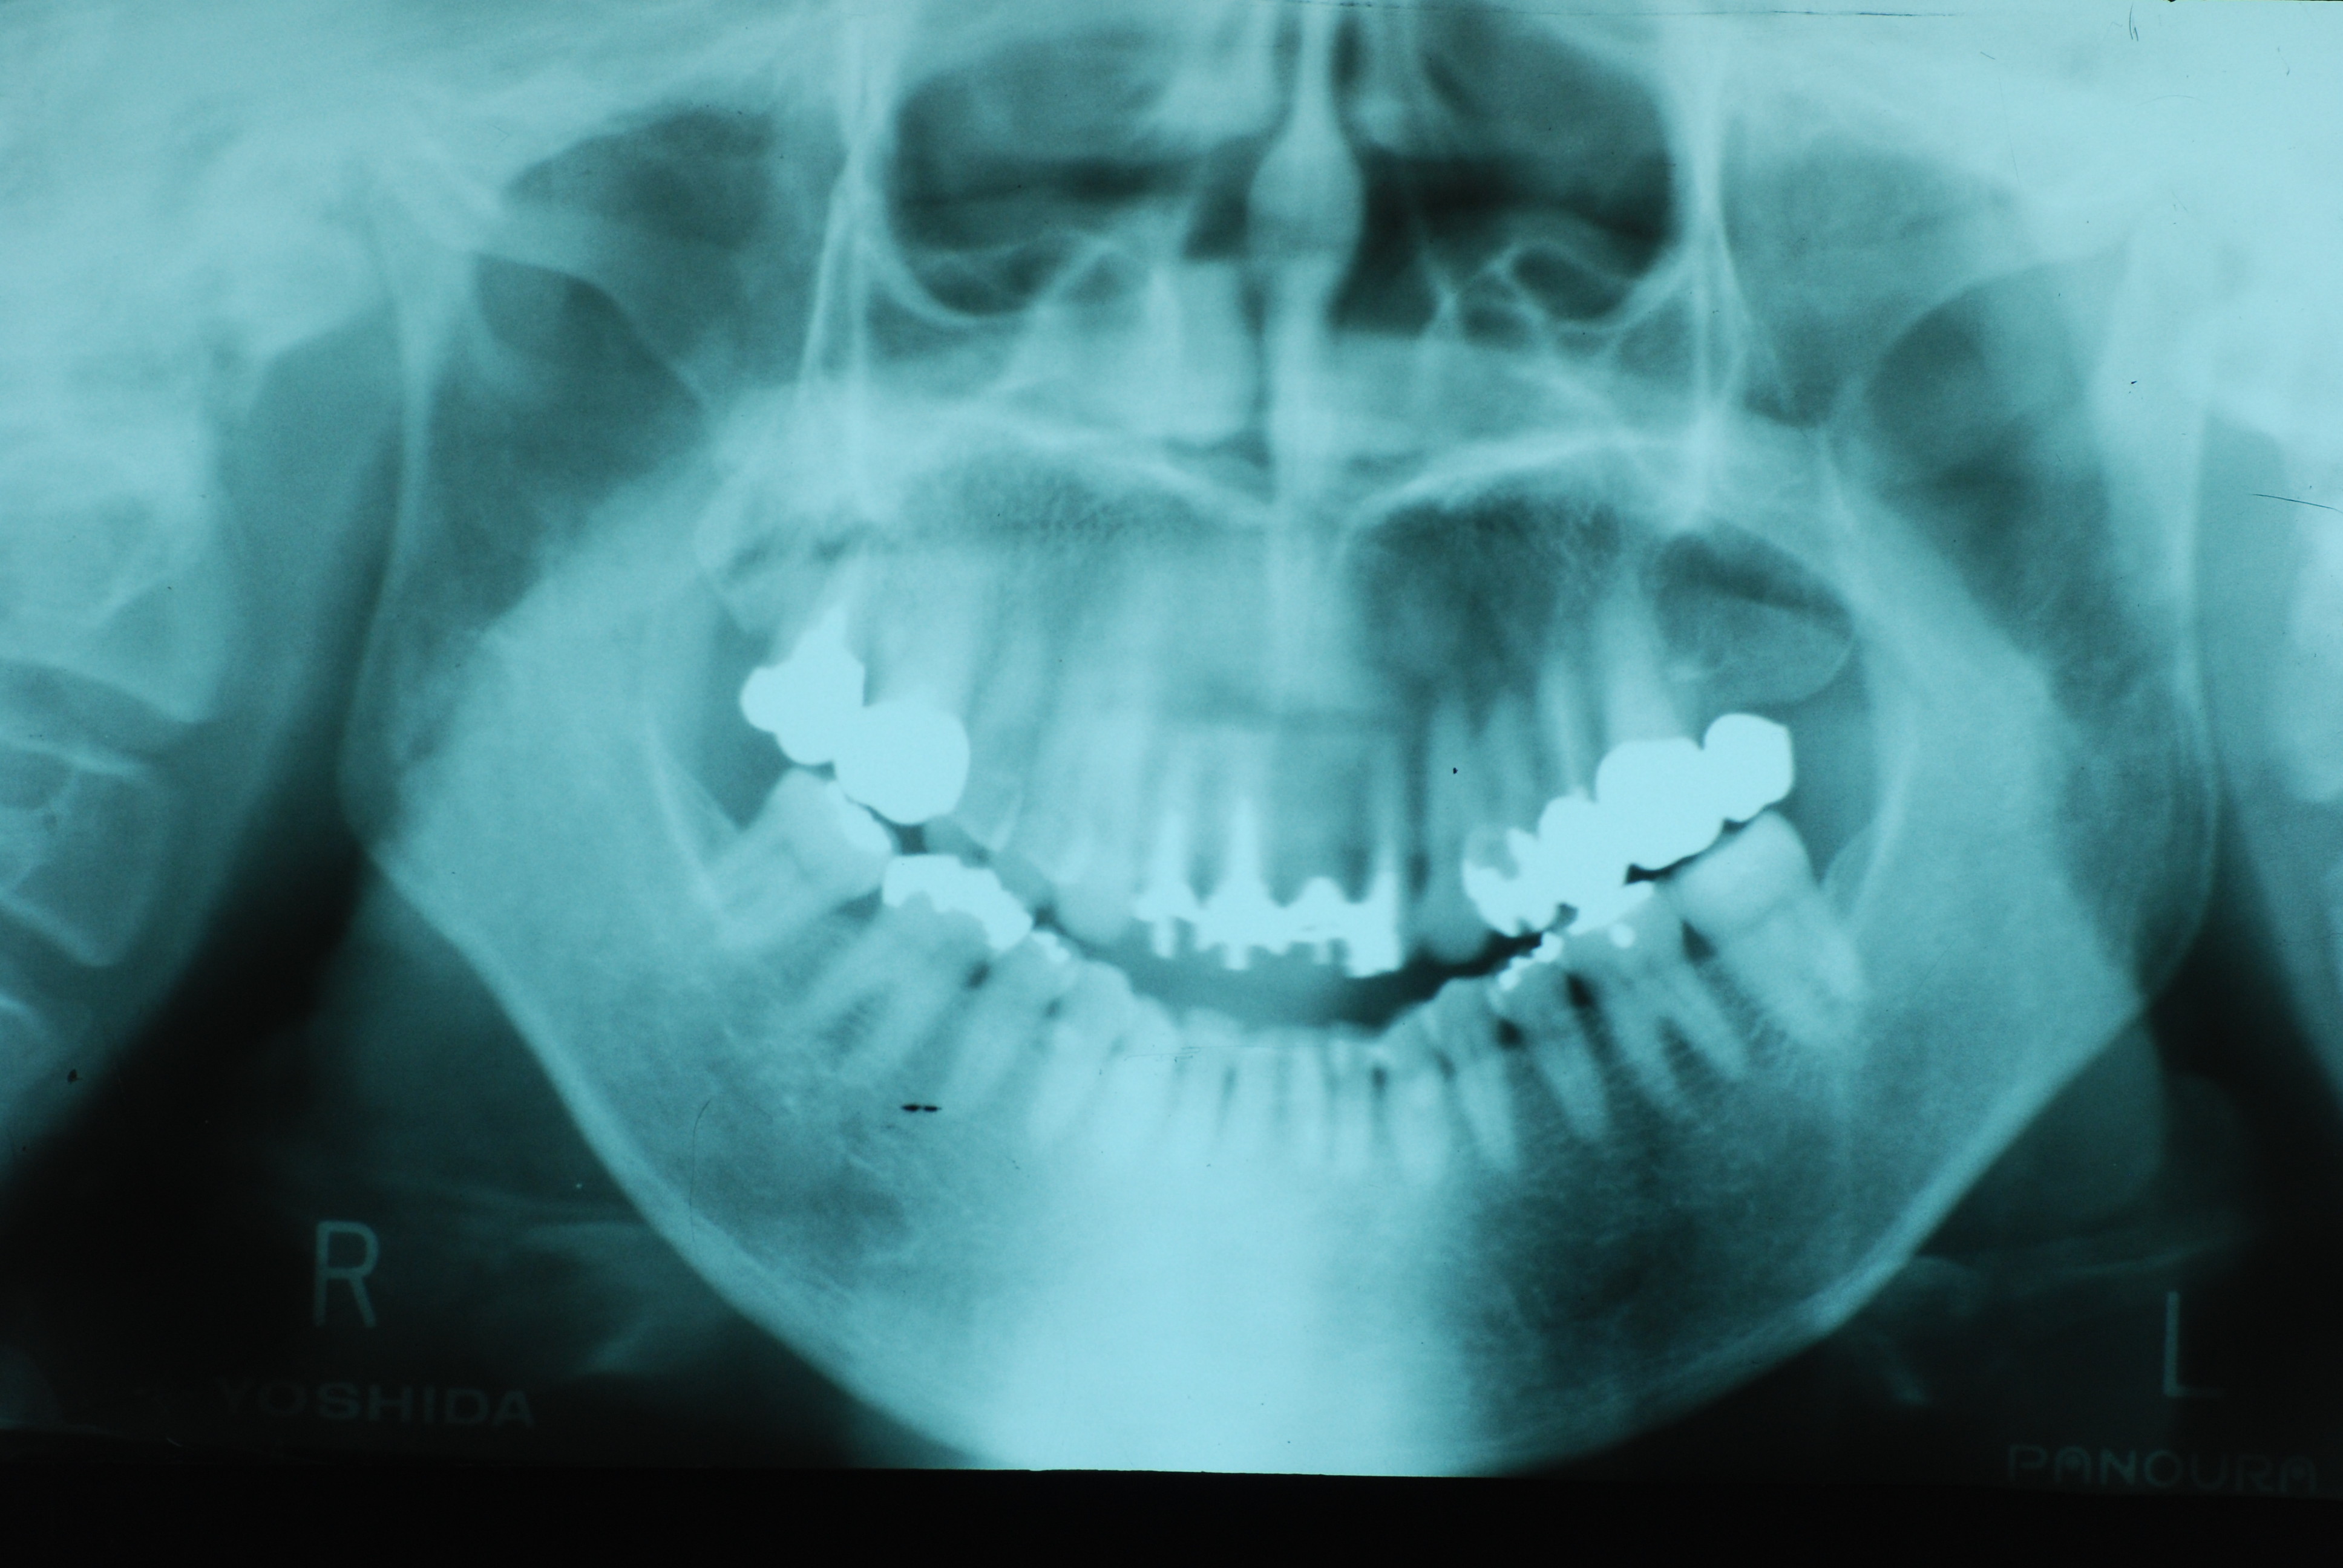

現実を見ればお口の中には“異物”である金歯、銀歯、セラミック、インプラントのオンパレードです。

これ等のものは、異物です。無い方が病気にならず健康でいられるのです。